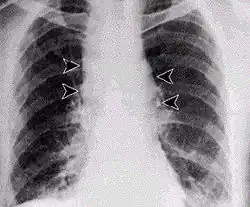

Najcięższa jest postać płucna (historycznie nazywana „chorobą sortowaczy wełny”) o charakterze ciężkiego zapalenia płuc. Ta postać charakteryzuje się wysoką gorączką, dreszczami, kaszlem z odpluwaniem krwistej plwociny, dusznością i sinicą. W znacznym procencie przypadków dochodzi do zgonu w okresie 24 do 36 godzin od wystąpienia objawów.

Na terenie ZSRR po zakończeniu wojny rozwijana była broń biologiczna, także zawierająca jako ładunek laseczki wąglika. Prace badawczo-produkcyjne w wojskowej fabryce broni B, działającej w programie „Biopreparat” (zobacz: Ken Alibek) w Swierdłowsku spowodowały w 1979 roku zakażenie ludności cywilnej (Katastrofa w Swierdłowsku; według nieoficjalnych danych zachorowało 79 osób, z czego zmarło 68). U 77 chorych wystąpiła płucna postać tej choroby (u 66 nastąpiło zejście śmiertelne). Innym ośrodkiem produkcji broni biologicznej z wykorzystaniem laseczek wąglika był Stepnogorsk w Kazachstanie. Sama produkcja jest trudna, wymaga dużej wiedzy i przede wszystkim odpowiedniego sprzętu.